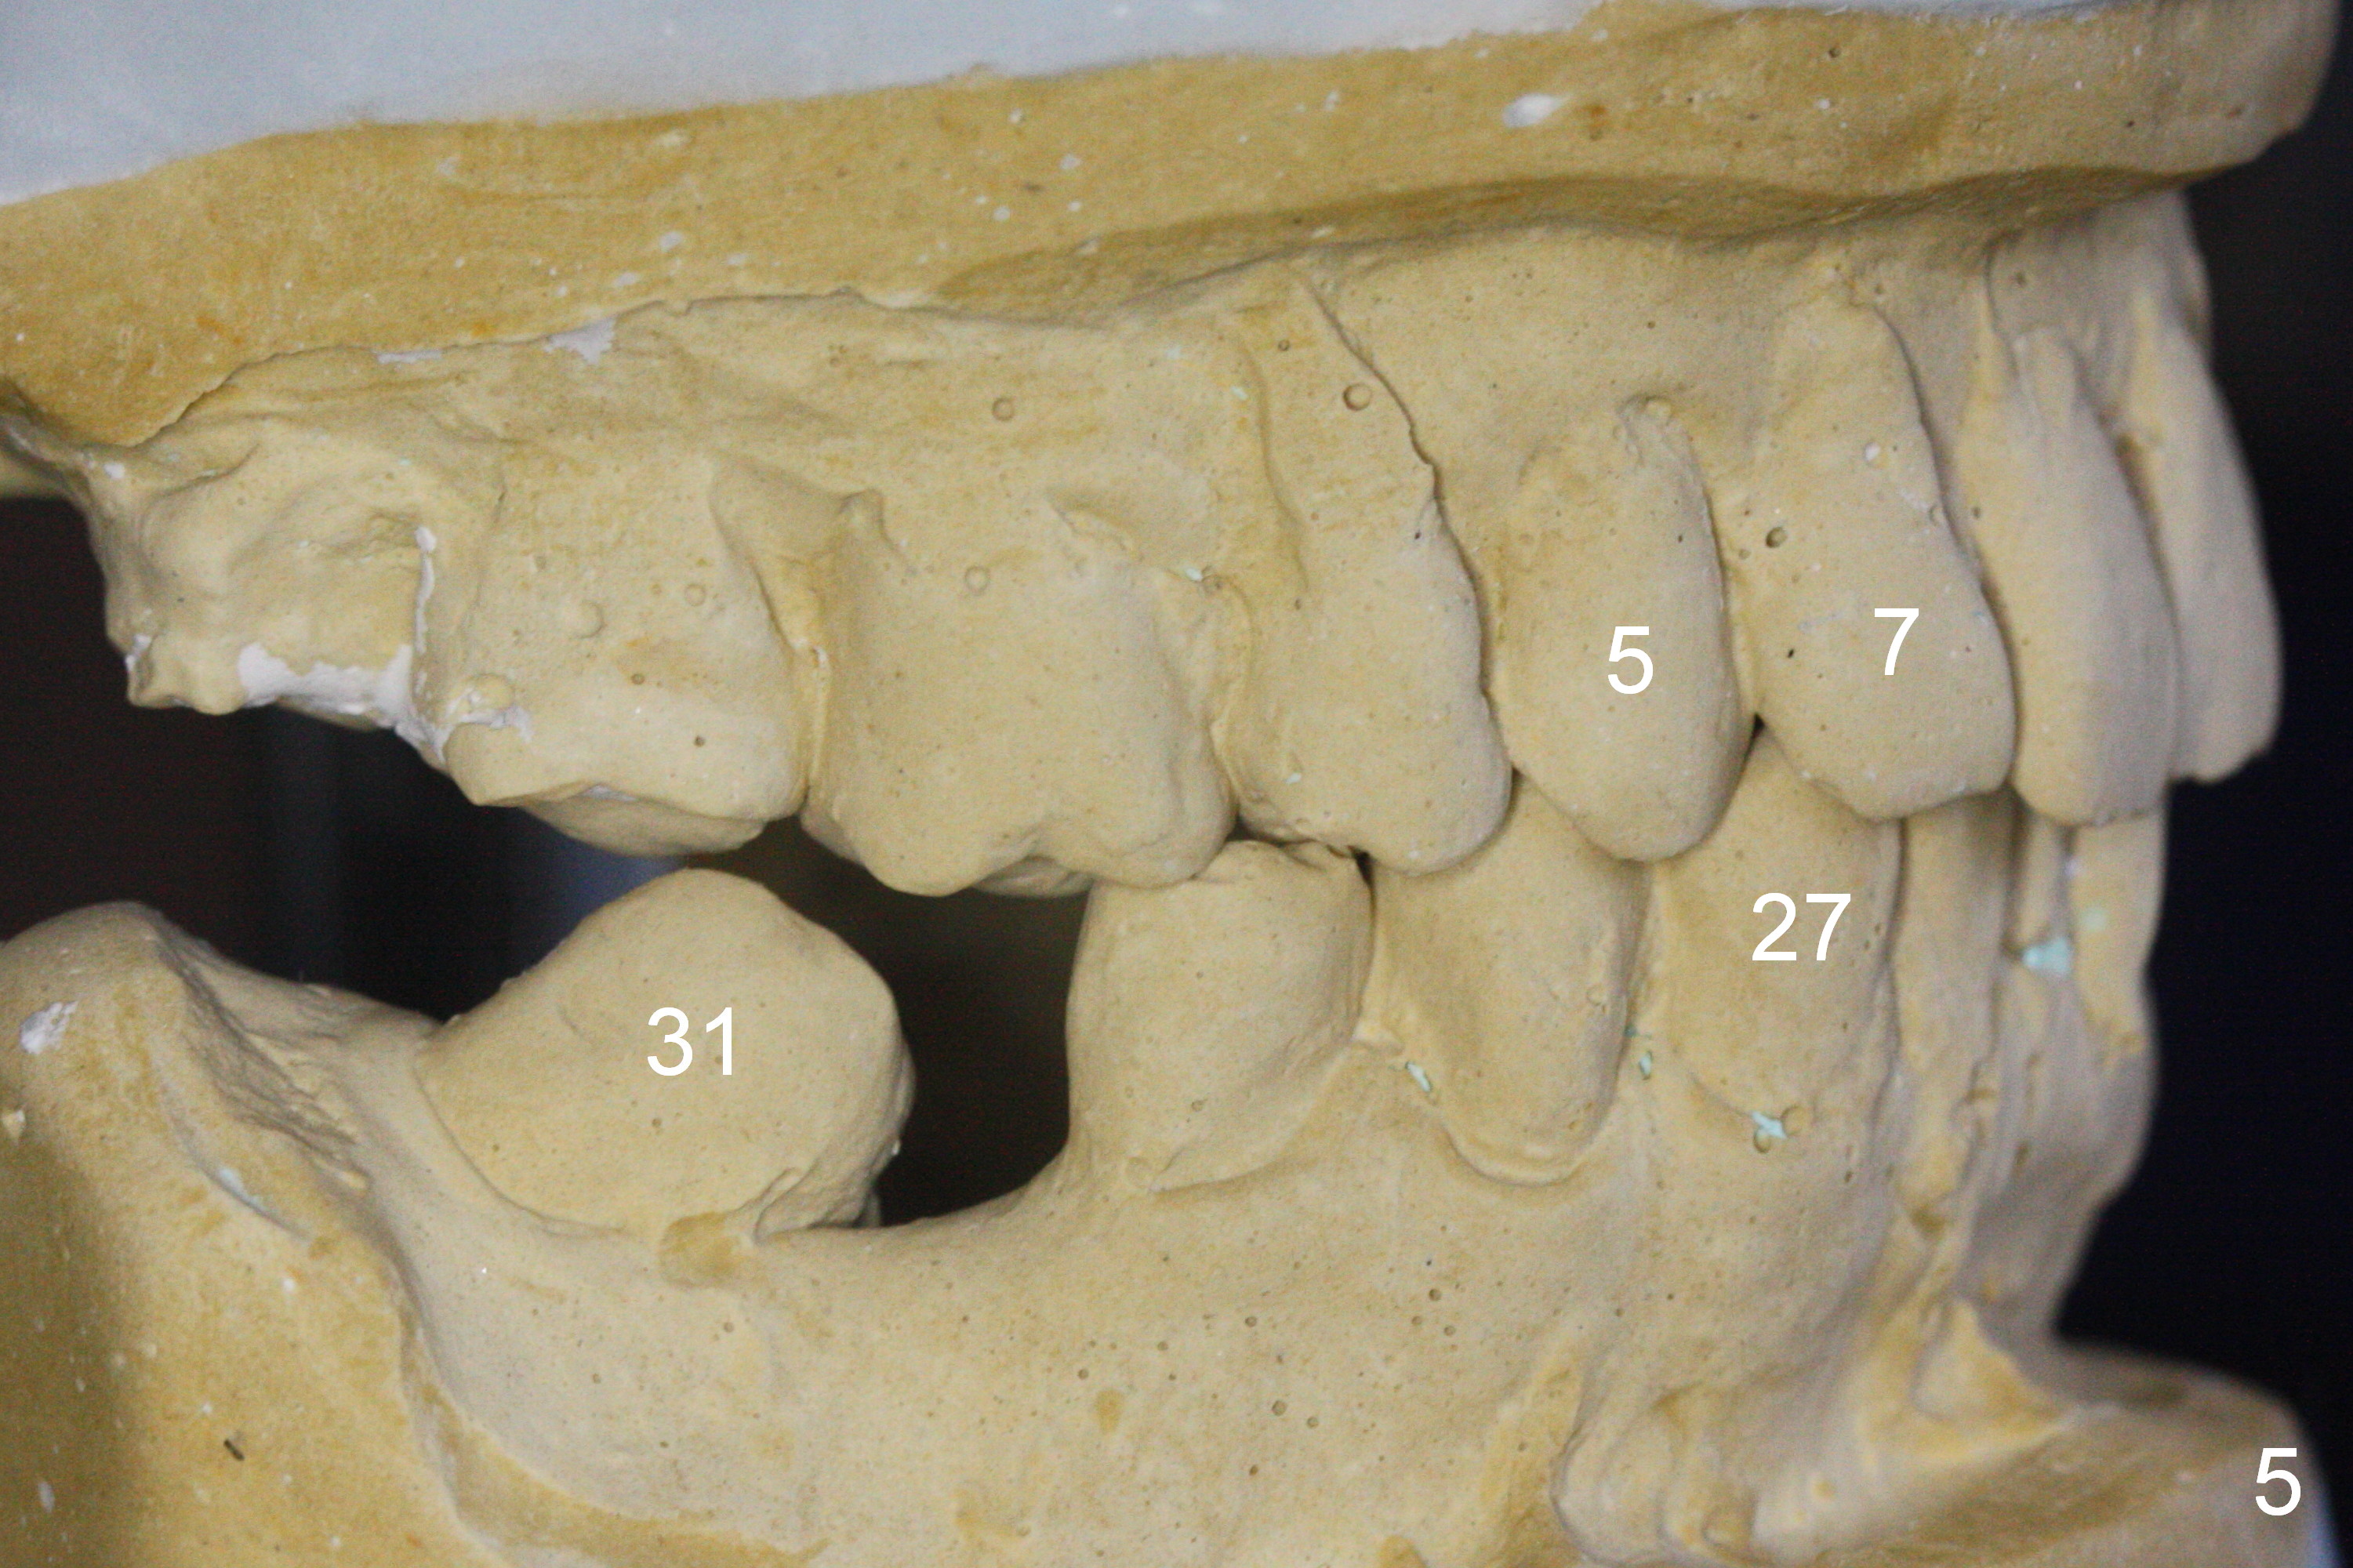

A 82-year-old man has pain in the lower left bridge. There is a buccal apical fistula associated with the tooth #17 (Fig.1). An immediate implant will be placed at #17 after bridge removal (Fig.2,3 blue). Once it osteointegrates, it will be used an anchorage (direct (instead of indirect), most efficient) to upright the tooth #18 (change the longitudinal axis from red line to purple one (Fig.4); white circle: center of resistance (rotation)). Then an implant will be placed at #19 (white rectangle).

Take Alginate impression and keep it moist. It will be used as a stent for temporization later on. After the tooth #17 is extracted with Clindamycin treatment, a FC dummy implant (5x9 mm) will be placed, followed by 6x4(2) mm abutment (Fig.3,4 pink). If there is severe vertical height issue, change to Magicore. Due to schedule conflict, prepare UF for this case instead.

One of the patient's daughter feels that the treatment is too complicated. She would like to have the 2nd molars extracted and implants at the 1st and 2nd molar sites (from Fig.5,6 to 7-9). Since the upper canines are missing (Fig.5,6), the final occlusion will be Class II posteriorly (Fig.8,9).